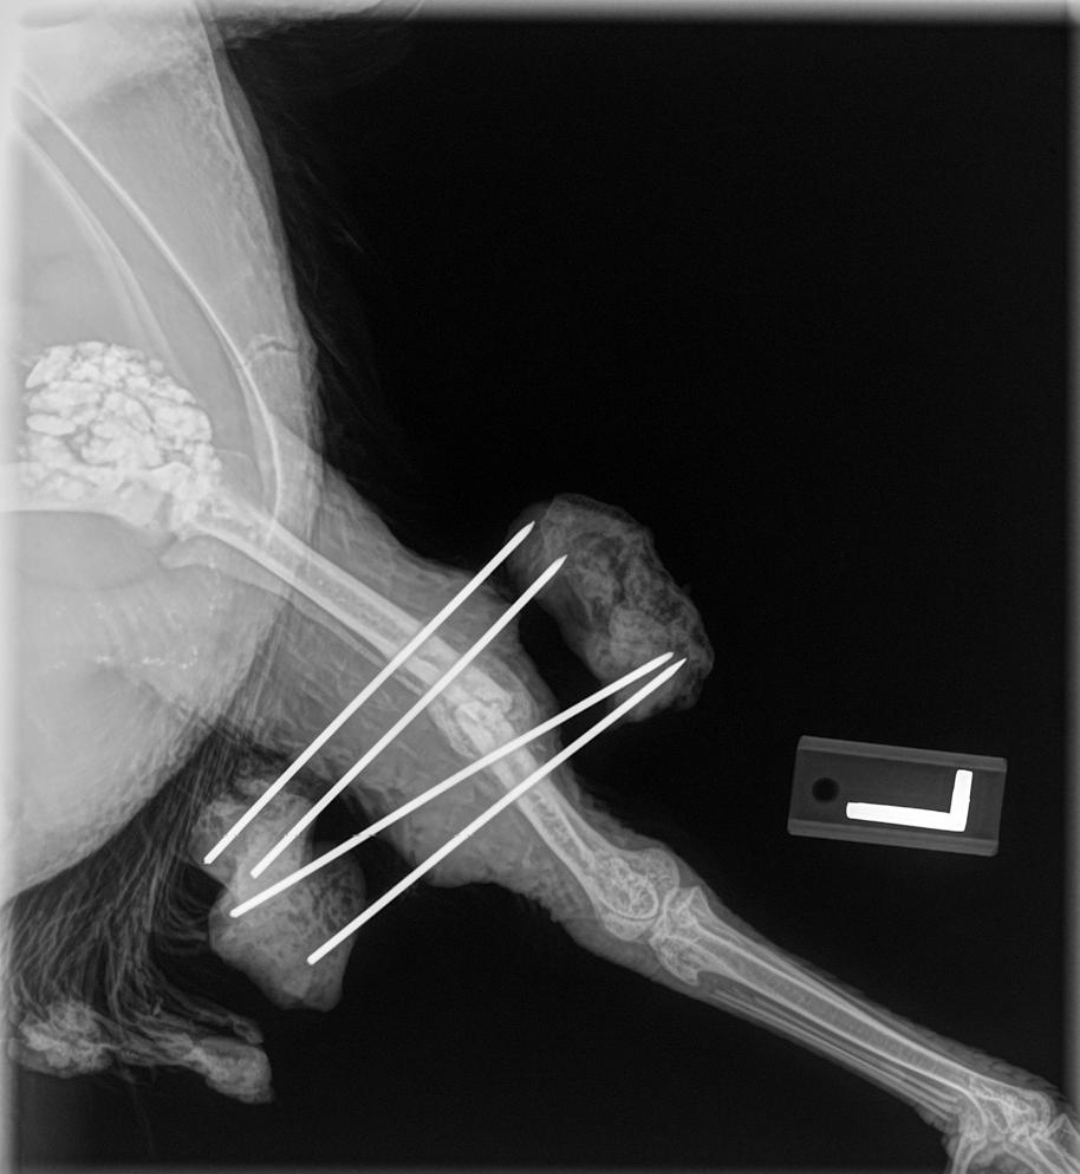

The vet technician plucked feathers off Raven’s leg and we were given an estimated time of 25-30 minutes for the surgery. It took an hour, as Dr. Jammie had to struggle with getting the two parts of the bone lined up properly and then pinned the leg with an external fixator device. Raven came out of surgery drooling a little and groggy, but traveled home well.

Week 4: We had another radiograph done. The healing was noticeable with new bone developing at the break, but it wasn’t strong enough yet.

Week 6: The pins were removed. Raven made a full recovery.